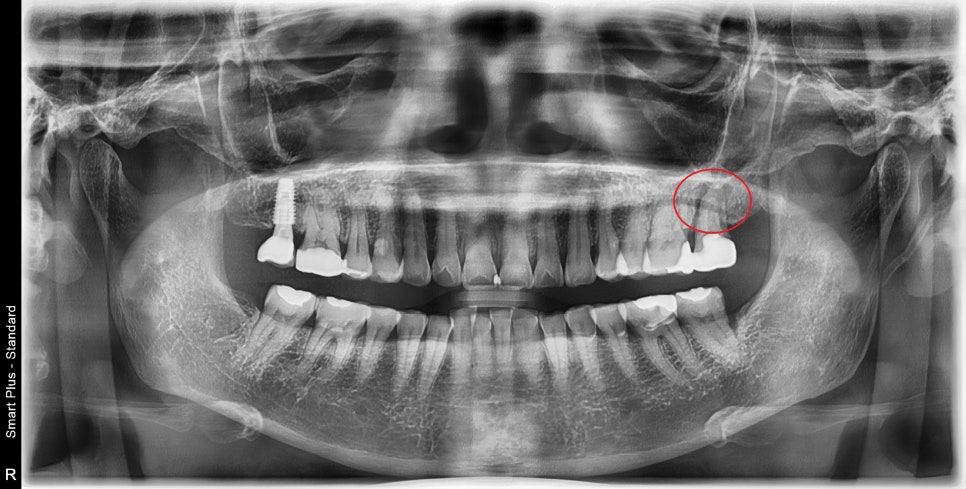

이미 엑스레이에서 근단부 염증이 심하시고, 입천장 쪽에는

고름 주머니까지 형성이 되어있었습니다.

동요도까지 생겨서 재 신경치료는 불가능해 보입니다.

발치 전 CT를 찍어 주변 치조골을 평가했습니다.